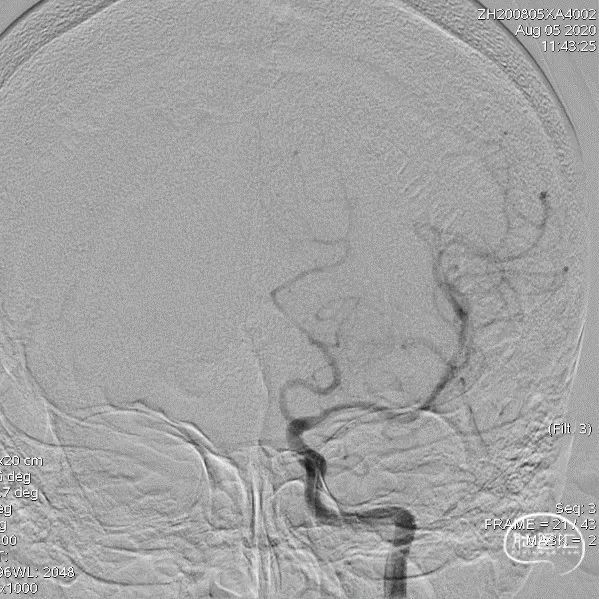

术前影像

术后即刻影像

术前影像

术后影像

术前影像

术后即刻影像